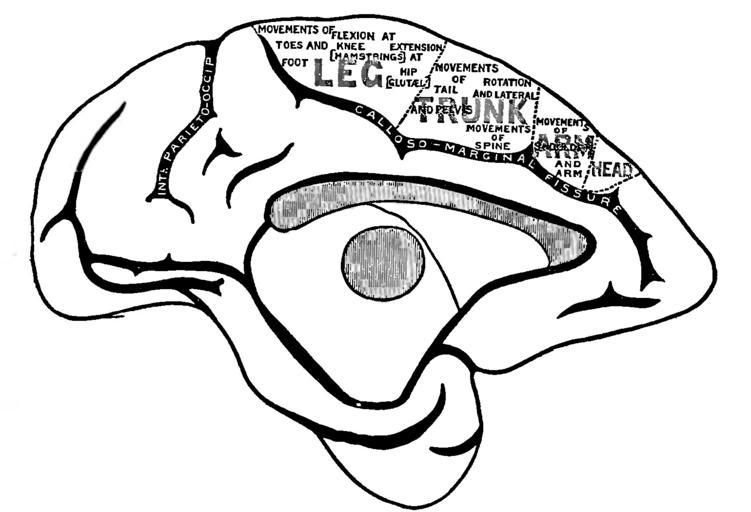

| Keywords: Principles of Psychology (James) v1 p35.png en The brain of the monkey <P>Fig 7 ”Left Hemisphere of Monkey's Brain Mesial Surface </P> <P>From the first edition of The Principles of Psychology by William James 1890 vol I page 35 <P> 1890 https //archive org/details/principlesofpsyc001jame Internet Archive scan of the book William James other versions PD-old-100-1923 Principles of Psychology 1890 Primate brain | ||||